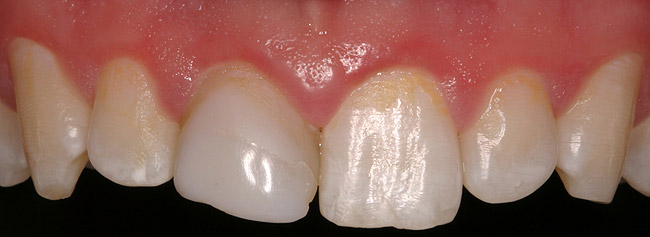

Figure 6a  Upper right central incisor, history of trauma, existing RCT and restoration unsatisfactory.

Figure 6a

Figure 6b  Upper right central incisor, history of trauma, existing RCT and restoration unsatisfactory.

Figure 6b

Figure 6c  Upper right central incisor, history of trauma, existing RCT and restoration unsatisfactory.

Figure 6c

Figure 6d Completed treatment: revised RCT, zirconium post/pressed ceramic core cemented with Panavia 21¬Æ Resin Cement (Kuraray Dental). All-ceramic full-coverage crown cemented with Kerr NX3 Nexus¬Æ Third Generation Dual Cure Resin cement. Implant therapy not indicated.

Figure 6d

Figure 6e  Completed treatment: revised RCT, zirconium post/pressed ceramic core cemented with Panavia 21¬Æ Resin Cement (Kuraray Dental). All-ceramic full-coverage crown cemented with Kerr NX3 Nexus¬Æ Third Generation Dual Cure Resin cement. Implant therapy not indicated.

Figure 6e

Figure 6f  Completed treatment: revised RCT, zirconium post/pressed ceramic core cemented with Panavia 21¬Æ Resin Cement (Kuraray Dental). All-ceramic full-coverage crown cemented with Kerr NX3 Nexus¬Æ Third Generation Dual Cure Resin cement. Implant therapy not indicated.

Figure 6f